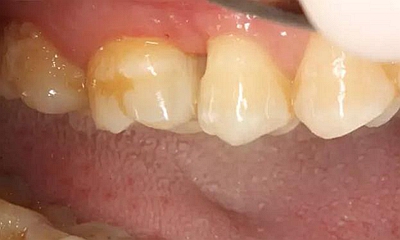

患者女性,55歲,3年前B3纖維樁+鑄瓷全冠修復,一周前牙冠折斷,就診后,發(fā)現(xiàn)纖維樁根管口處折斷,周圍牙齦增生,建議患者行冠延長手術。首先去除斷端的纖維樁。拍片示牙根長度充足。于是開始冠延長手術。

因為是前牙,故該患者將來修復體邊緣必須為齦下,所以3個月后再行修復。以下為手術前照片。

以下為術中照片。

內(nèi)斜切口,頸圈組織,改良垂直褥式縫合。